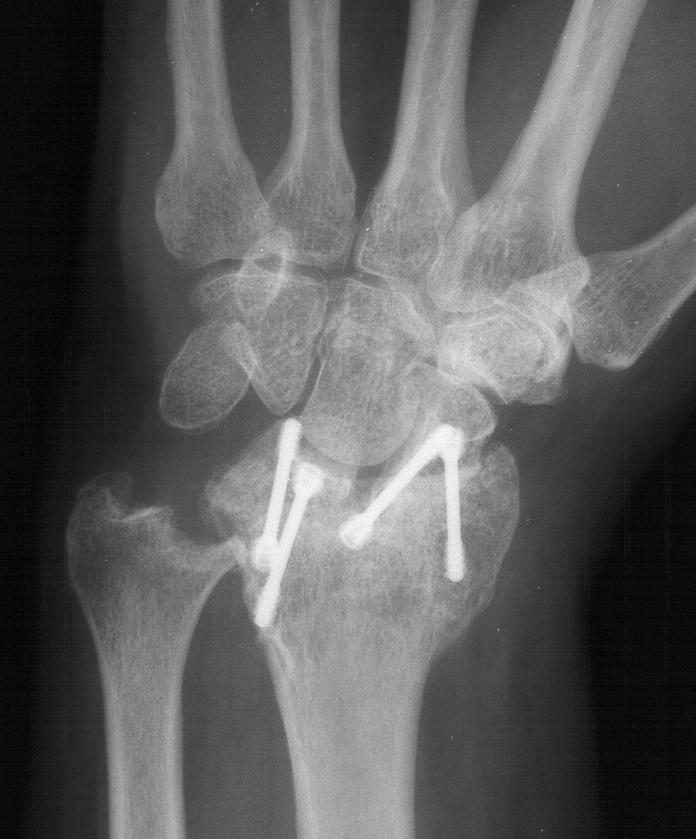

Preoperative Xrays:

Radioscapholunate fusion is a treatment option for radiocarpal arthritis following distal radius fracture or associated with rheumatoid arthritis. Range of motion is usually less than half of normal following this procedure. Technical modifications to improve range of motion include distal scaphoid excision, or as in this case, triquetrum excision and excision of distal ulnar articular surface to manage ulnolunate abutment. There are a variety of fixation techniques. In this case, crossed Herbert screws were used: dorsal carpal bone to palmar radius and dorsal radius to palmar carpal bone.